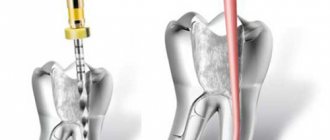

Before filling the canal, pulp and softened, infected dentin are removed from the root canal of the tooth.

The canal is carefully treated mechanically and with medications.

A cannula can be inserted almost completely into a wide straight channel and a portion of Calcept paste (with iodoform) can be squeezed out, and then condensed using the usual method.

In curved canals, Calcept paste (with iodoform) is applied to the mouth of the canal and tightly condensed inside with endodontic instruments or sterile turunda.

The better the paste is condensed, the better the radiopacity of the material on the radiograph. It is enough to fill the canal up to the top, and in poorly passable canals the entire passable part, with a developed growth zone, 1-2 mm short of reaching the top of the canal. When removing the material beyond the root tip, no problems arise due to the high alkalinity and complete immunoindifference of the material. Next, the cavity is closed with cement.